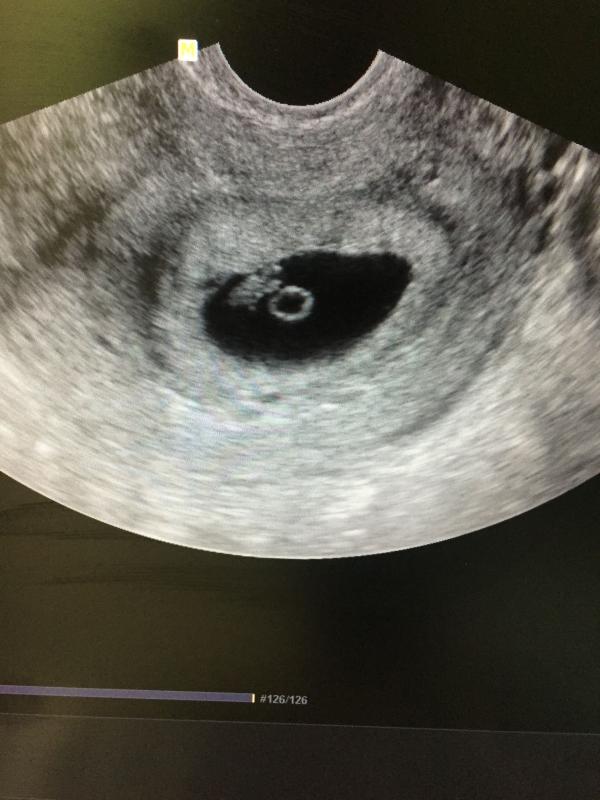

Добре утро , мои дорогие 🙏🏻☺️😍 я счастлива !!! Увидела я своего малыша и сердечко услышала ❤️❤️❤️🙏🏻🙏🏻🙏🏻😇 по УЗИ 6 недель и 5 дней , все хорошо ) значит была поздняя овуляция . Анализы у меня все хорошие , тьфу тьфу тьфу ... тонуса и угрозы нет 🙏🏻☺️ единственное плодное яйцо очень очень низко прикрепилось (( но наверное это не самое страшное теперь ... завтра иду вставать на учёт 🙏🏻😍 девочки , я самая счастливая 😍 спасибо всем кто поддерживал и верил что у меня все будет хорошо ☺️❤️ завтра отпишусь как схожу ...